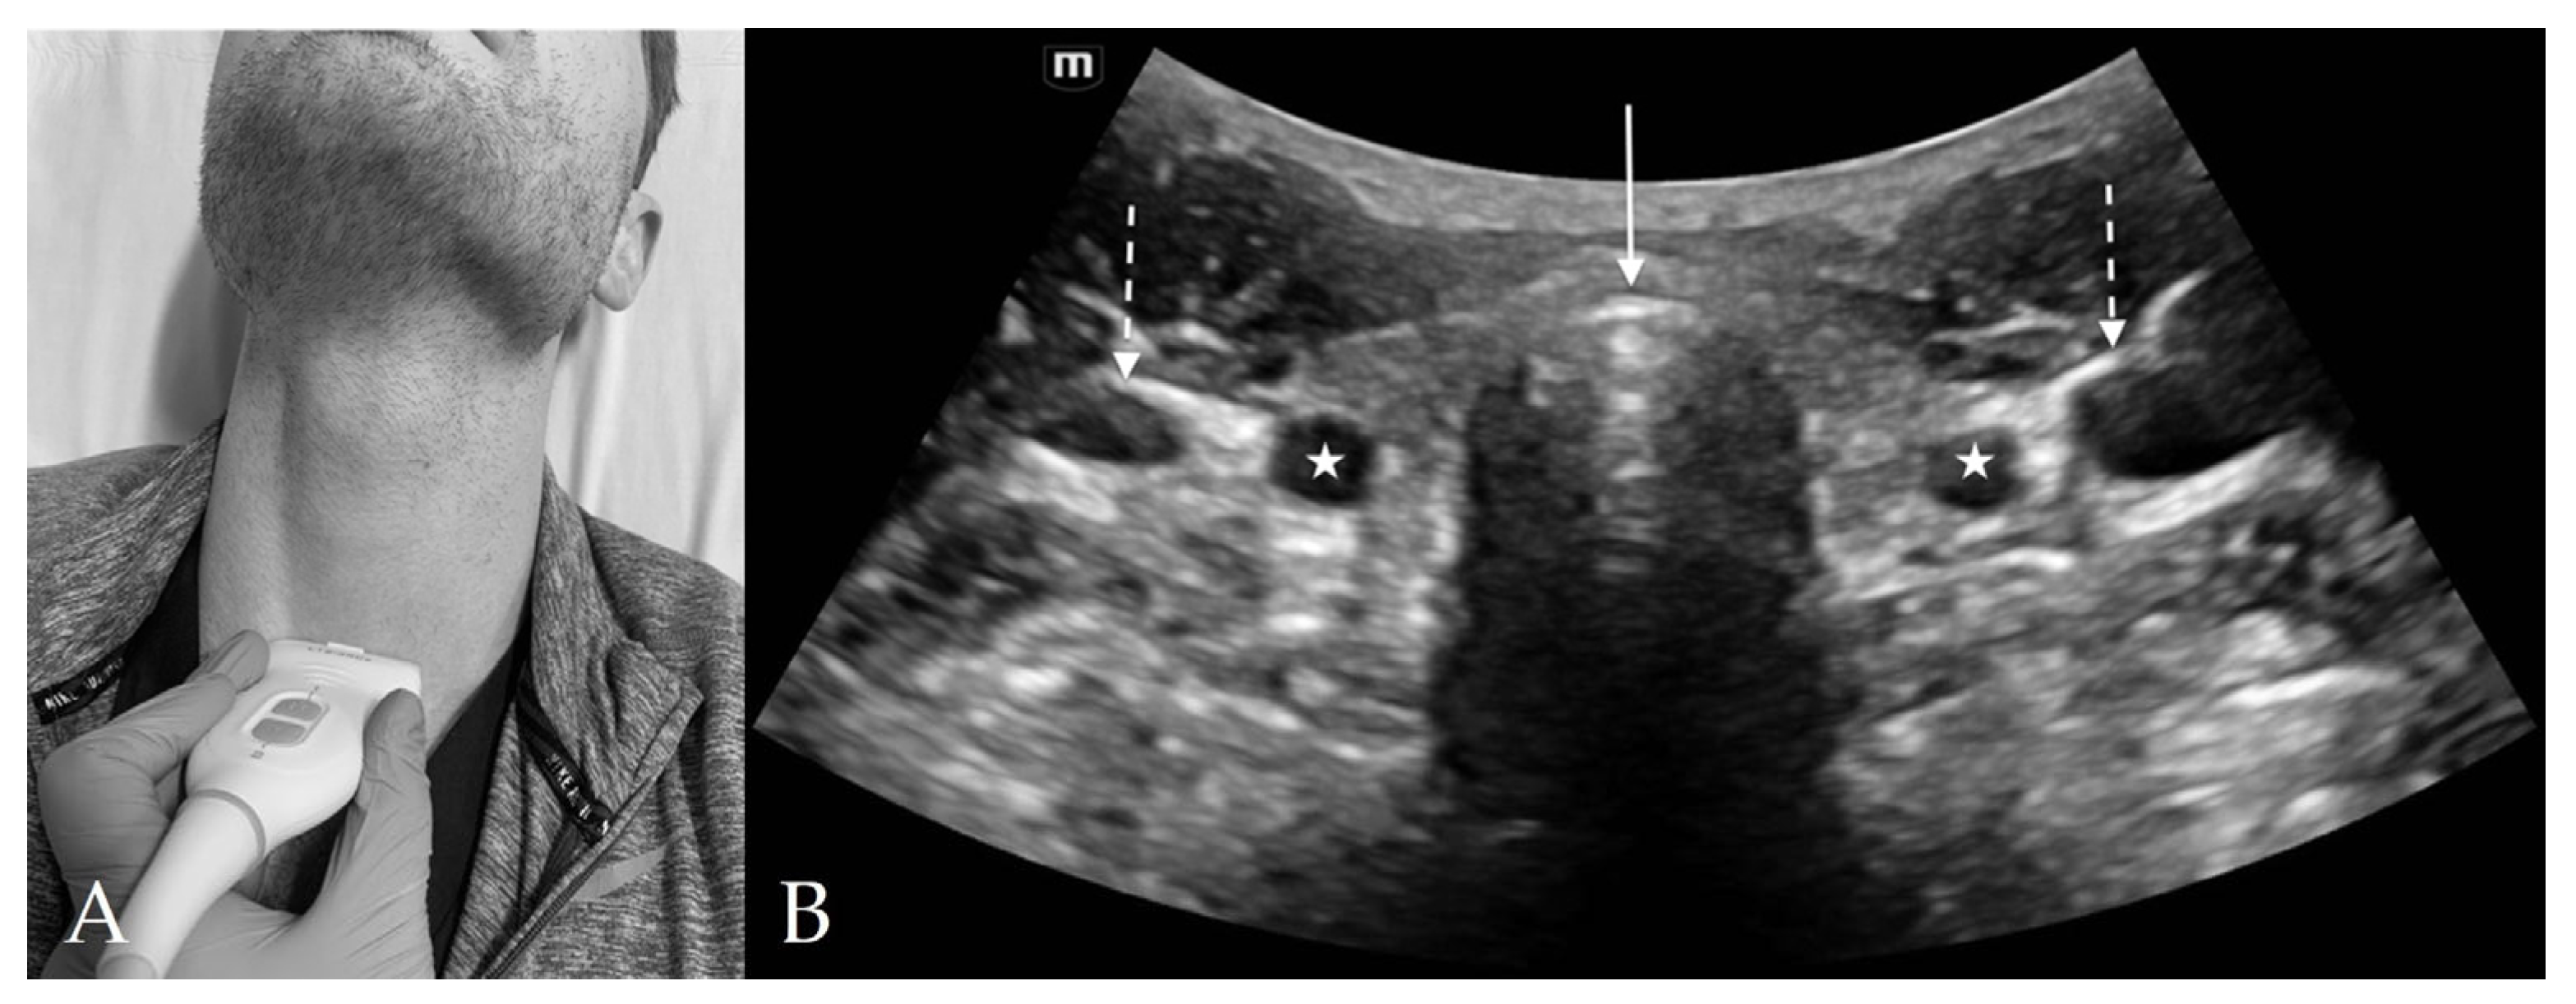

3. Probe Selection and Technique

4.3. Thyroid View